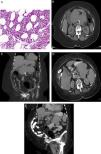

Presentación del casoMujer de 69 años de edad con colangitis aguda es traslada al servicio de urgencias, presentando fiebre, dolor en cuadrante superior derecho de abdomen e ictericia, con paraclínicos demostrando bilirrubina sérica total de 5mg/dl, fosfatasa alcalina de 159mg/dl, ALT de 41UI/dl y AST de 38UI/dl. Con antecedente familiar de muerte secundaria por cáncer de páncreas, y antecedentes personales de plasmocitoma que se manifiestaron como una fractura patológica en el radio derecho y la columna lumbar, hace 5 años, la cual recibió tratamiento quirúrgico y administración de radio-quimioterapia (melfalán y prednisona). Tres años después, se observaron células de mieloma en la médula ósea, por lo que recibió un nuevo esquema de quimioterapia (vincristina, doxorubicina y dexametasona) lograndosé una respuesta parcial. En la hospitalización actual, durante la colangiografía endoscópica retrógrada (CPER) no fue posible realizar la canulación biliar debido a una compresión externa del conducto biliar principal. Se administraron antibióticos de amplio espectro. La tomografía computarizada (TC) mostró un tumor de páncreas de 12×7×8cm, con dilatación de la vía biliar e involucró de la vena mesentérica superior y el duodeno, se realizó una biopsia guiada por TC, observandosé infiltración de mieloma en la histología pancreática (fig. 1), por lo que se inició tratamiento con melfalán, prednisona y talidomida. El seguimiento fue durante los 8 meses posteriores, mostrando la desaparición de la ictericia, la normalización de la bilirrubina y los niveles séricos de la fosfatasa alcalina, y la reducción del 50% del tamaño del tumor (figs. 1A-D). La paciente, actualmente, se encuentra sin recurrencia de la colangitis.

A) CD138 inmunohistoquímica mostró tinción positiva en células plasmáticas. B) Antes de la radioterapia. Una TC mostró un compromiso pancreático difuso de 13×7×8cm (flecha), que causa una compresión externa del estómago y del duodeno. C) Antes de la radioterapia: una reconstrucción coronal por TC revela un involucro pancreático difuso (flecha). D) Despues de la radioterapia: la TC revela más del 50% de disminución del tamaño de la masa pancreática (flecha). E) Después de la radioterapia: una reconstrucción por TC revela disminución del más del 50% del tamaño de la masa.